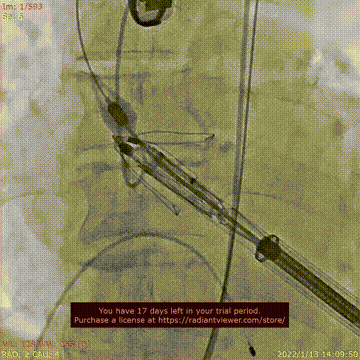

瓣膜释放过程

术后DSA影像图